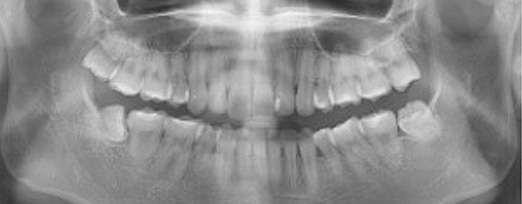

충치치료

정확한 진단으로 꼭 필요한 충치치료만을 진행합니다

충치치료는 정확하고 객관적인 진단이 가장 중요하며, 충치의 진행단계별로 적합한 치료를 진행해야 합니다.

충치가 있다는 말과 충치치료를 해야한다는 말이 같은 뜻은 아닙니다. 까맣게 보인다고해서 무조건 제거하고 떼워야하는 것은 아닙니다.

초기 충치의 경우 충치를 제거하기보다 그 충치가 더 진행되지 않게 예방하는 것이 더 중요하며, 이는 자연치아를 최대한 보존하고 불필요한 치료를 방지하는 방법입니다. 이를 위해서는 객관적이고 정확하게 충치의 단계를 진단하는 것이 필수적입니다.

청담네오플란트에서는 전문의료진들이 첨단 의료장비와 객관적인 시각자료를 통해 충치의 단계를 정확하게 진단하여 환자분들께 자세한 설명을 드린 후 단계 별로 꼭 필요한 치료만을 진행하고 있습니다.

법랑질 충치

치아는 자각증상이 없을 수도 있음.

이 시기의 충치는 반드시 제거해야할 필요는 없으며 정기적 관찰과 예방 및 비침습적인 치료를 통해 충치의 진행단계를 늦추거나 멈출 수 있음.

치료방법 예방치료인 실란트, 불소도포, 정기검진

상아질 충치

찬 공기나 물에 닿을 때나 양치시

자각증상이 있을 수 있으며, 치아가 음푹 패이거나 삭을 수 있음. 치료하지 않으면 충치의 진행이 빨라질 수 있음.

치료방법 레진 충전, 인레이 등 수복치료

치수염 충치

밤에 잠을 이루지 못할 정도로 아프거나 찬 것과 뜨거운 것에 통증이 있을 수 있으며, 도중에 나은 것처럼 증상이 없어지는 경우도 있음. 치아의 경조직 뿐 아니라 치수까지 염증이 생긴 상태.

치료방법 신경치료, 크라운 등 보철치료